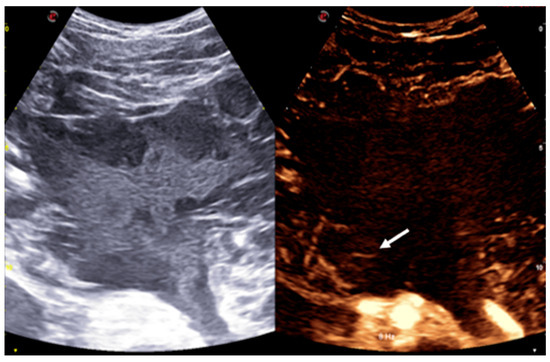

The patient was subsequently admitted for further evaluation, and an abdominal MRI was performed. Imaging sequences included T2-weighted sequences and T1-weighted sequences, with and without fat suppression. However, due to limited patient compliance, the study was interrupted before the contrast agent administration. Despite these limitations, MRI confirmed the presence of a large multiloculated mass with peripheral cystic components exhibiting fluid-debris levels (Figure 2).

Given the imaging characteristics and the broad differential diagnosis, including both benign and malignant entities, an ultrasound-guided biopsy was performed under contrast-enhanced ultrasound (CEUS) guidance. The mass itself showed no contrast uptake, except for some peripheral septa, which exhibited mild contrast enhancement (Figure 3).

The lesions present distinct imaging characteristics across different modalities. On US, they typically appear as hypoechoic or anechoic multiloculated cystic spaces with thin septa. There is usually no blood flow within the lesion on color Doppler, except in the septa, where high-resistance arterial or venous flow can sometimes be seen [6].

On MRI, these malformations are usually well-defined, lobulated, and septated. They predominantly show low signal intensity on T1-weighted images and high signal intensity on T2-weighted images. The signal intensity can vary depending on the amount of protein or hemorrhage in the lesion. Occasionally, the content may appear brighter than muscle on T1-weighted images, particularly in cases where the cyst contains protein or blood. Generally, the enhancement after contrast medium agent administration is visible only in the septa and solid components. However, if there is inflammation, the septa surrounding areas may also show significant enhancement [6].

Figure 2. The multiloculated mass shows variable signal intensity on T2 sequences and presents cystic formations peripherally, exhibiting fluid-debris levels (thick arrow). Some calcified spots with low T2WI signals were also noted within the mass (thin arrow).

Figure 3. CEUS shows a multicystic lesion composed of individual cysts surrounded by a debris-filled matrix that does not enhance after contrast administration, except for some of the more peripheral septa, which demonstrate mild contrast enhancement (arrow).